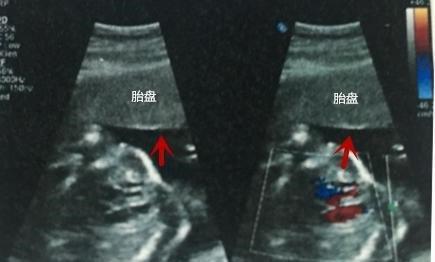

PL:胎盘

胎盘位置是说明胎盘在子宫壁的位置,正常足月胎盘的厚度应在2.5~5厘米之间。

GP :胎盘分级

Ⅰ级为胎盘成熟的早期阶段,回声均匀,在怀30~32周可见到此种变化;

Ⅱ级表示胎盘接近成熟;

Ⅲ级提示胎盘已经成熟,胎盘内有很多钙化点,表现为小砂粒状,一般不对胎儿生命构成威胁,但应引起重视。越接近足月,胎盘越成熟,回声的不均匀。